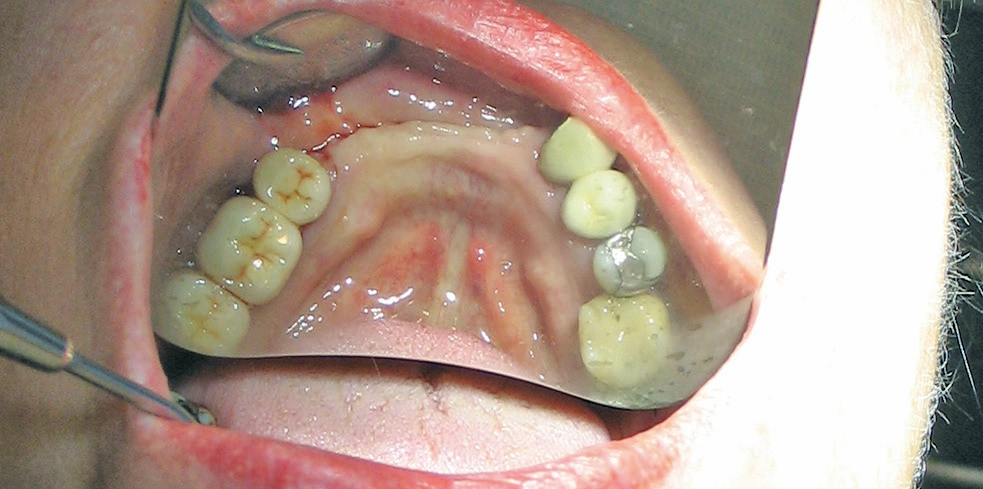

Für die Suprakonstruktionen wurde das Sekundärgerüst auf Abutment-Niveau gefräst. Der Patient bekam im Oberkiefer ein System mit interner Sechskantverbindung (Abb. 9-16). Die Patientin im Unterkiefer bekam ein System desselben Herstellers mit konischer Abutmentverbindung (Abb. 1-8). Davon ist ein Implantat noch in der Einheilphase verloren gegangen. Der betroffene Kiefer konnte trotzdem mit fünf Implantaten versorgt werden. Vom Prinzip „all-on-4“ wurde bewusst Abstand genommen. Ebenso wurde auch auf geneigt gesetzte Implantate verzichtet. Die Implantate, die abgewinkelte Abutments bekamen, wurden nach den prothetisch und anatomisch günstigsten Knochenverhältnissen gesetzt.

Für den Oberkiefer standen zwei Möglichkeiten zur Verfügung: 1. Abformung auf Implantatniveau, 2. Abformung auf Multiunit- Abutmentniveau. Wir haben die Variante zwei durchgeführt; dadurch wurden die richtigen Abutments ausgesucht, eingesetzt und nie wieder entfernt.